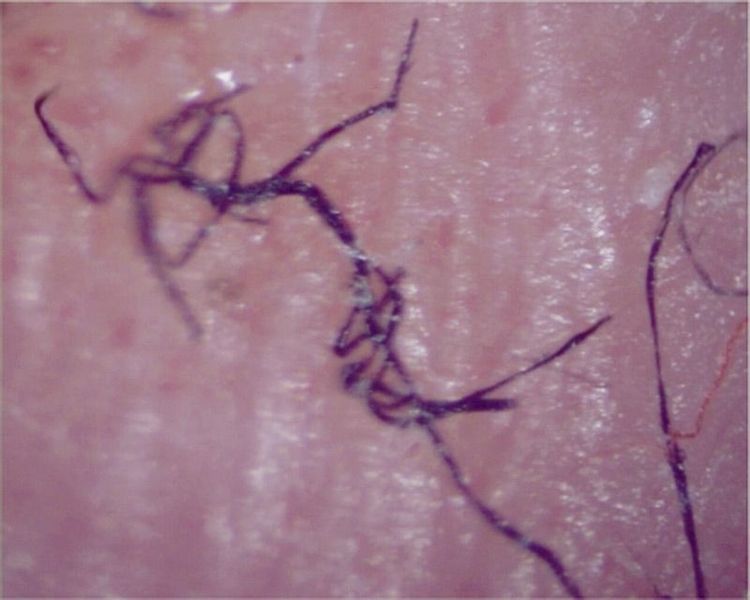

13. Болезнь Моргеллонов

Пациенты жалуются, что под кожей что-то ползает, а из ран появляются волокна или нити.

Часть учёных считает это психическим расстройством, другие — загадочной инфекцией. В 2000-х Центр по контролю заболеваний США провёл масштабное исследование, но не смог установить происхождение болезни.